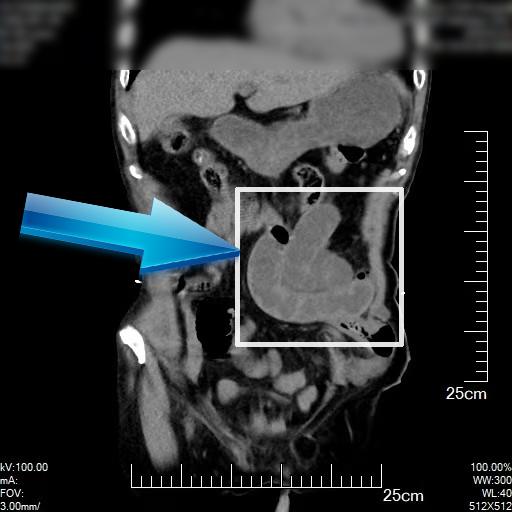

▲患者CT影像,右侧造瘘口旁小肠水肿梗阻

当即大爷被送入昆山市中医医院急诊外科。外科主治医师接诊后发现,患者腹部膨隆如鼓,压痛明显,结合 CT 影像和既往手术史,初步诊断为 “肠梗阻、结肠造口旁疝、腹内疝”。